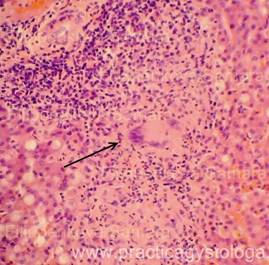

Рис. 1, 2. Картина очагового острого гнойного межуточного миокардита: очаговая и очагово-диффузная инфильтрация стромы миокарда сегментоядерными нейтрофильными лейкоцитами в различной степени выраженности, лейкоциты как чётко контурирующиеся, так и в состоянии распада. Отдельные кардиомиоциты и мелкие их пучки в состоянии некроза. Окраска: гематоксилин-эозин. Увеличение х100, х250.